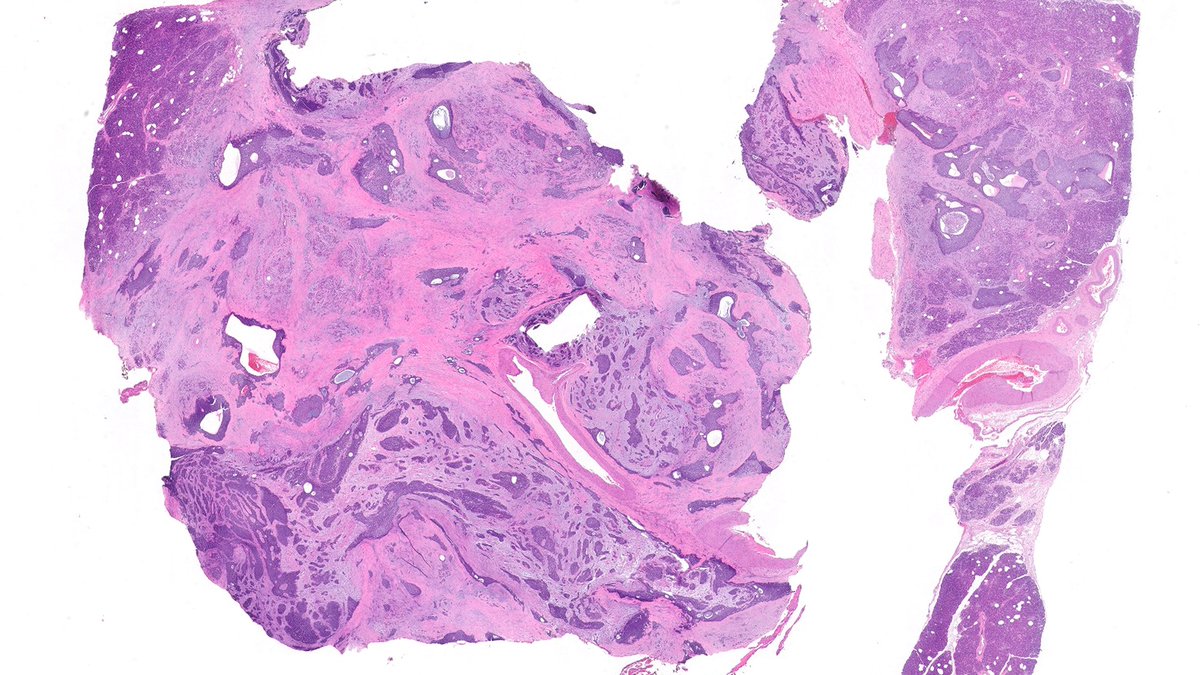

Oh Boy! This is a stunner. Pancreatic tumor. Youngish person. Diffusely keratin positive. Was called a poorly differentiated carcinoma. Sounds reasonable? #GIpath

Vik_deshpandeMD's tweet image. Oh Boy! This is a stunner.  Pancreatic tumor. Youngish person. Diffusely keratin positive. Was called a poorly differentiated carcinoma. Sounds reasonable? #GIpath